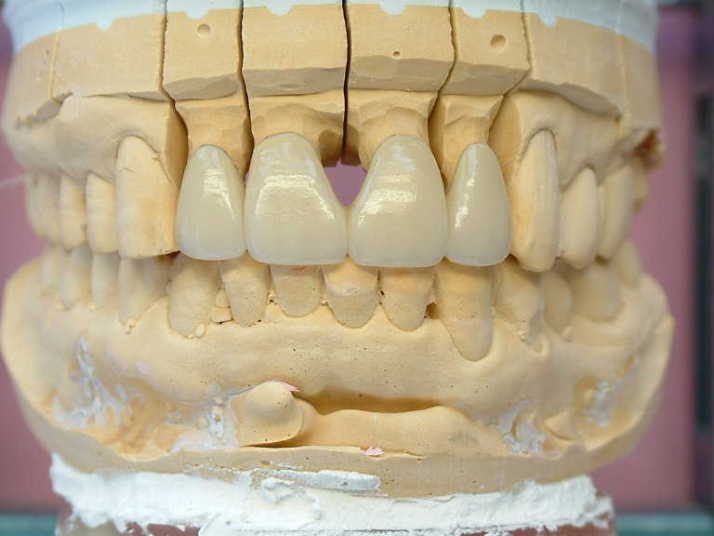

メタルコアー 個歯トレー&各個トレにて印象 |

補綴物物 完成

模型上では、1.1下部孤形空隙が広いように

見えますが、歯肉模型にて調整して

歯肉を圧迫せず、息が漏れることが無いように

調整しました |